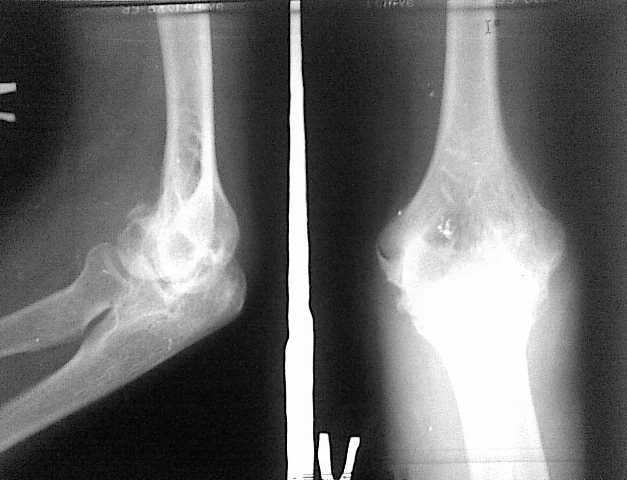

Риторический вопрос - если возможно, то хотелось бы посмотреть все снимки на этапах лечения. В данном сегменте даже при очень сложных переломах, при использовании накостного остеосинтеза достигаются очень приличные результаты. Привожу рентгенограммы пациентки. Операция проведена через 3 недели после травмы. На сегодняшний момент 3 недели после остеосинтеза. Движения сгибание до 60 градусов, разгибание 150-160. Мое мнение, что спицы и 45 суток в гипсе это несколько грубо для такого "капризного" локтевого сустава.

Кликните для загрузки файла локоть 1.jpg

16KB (17325 bytes)